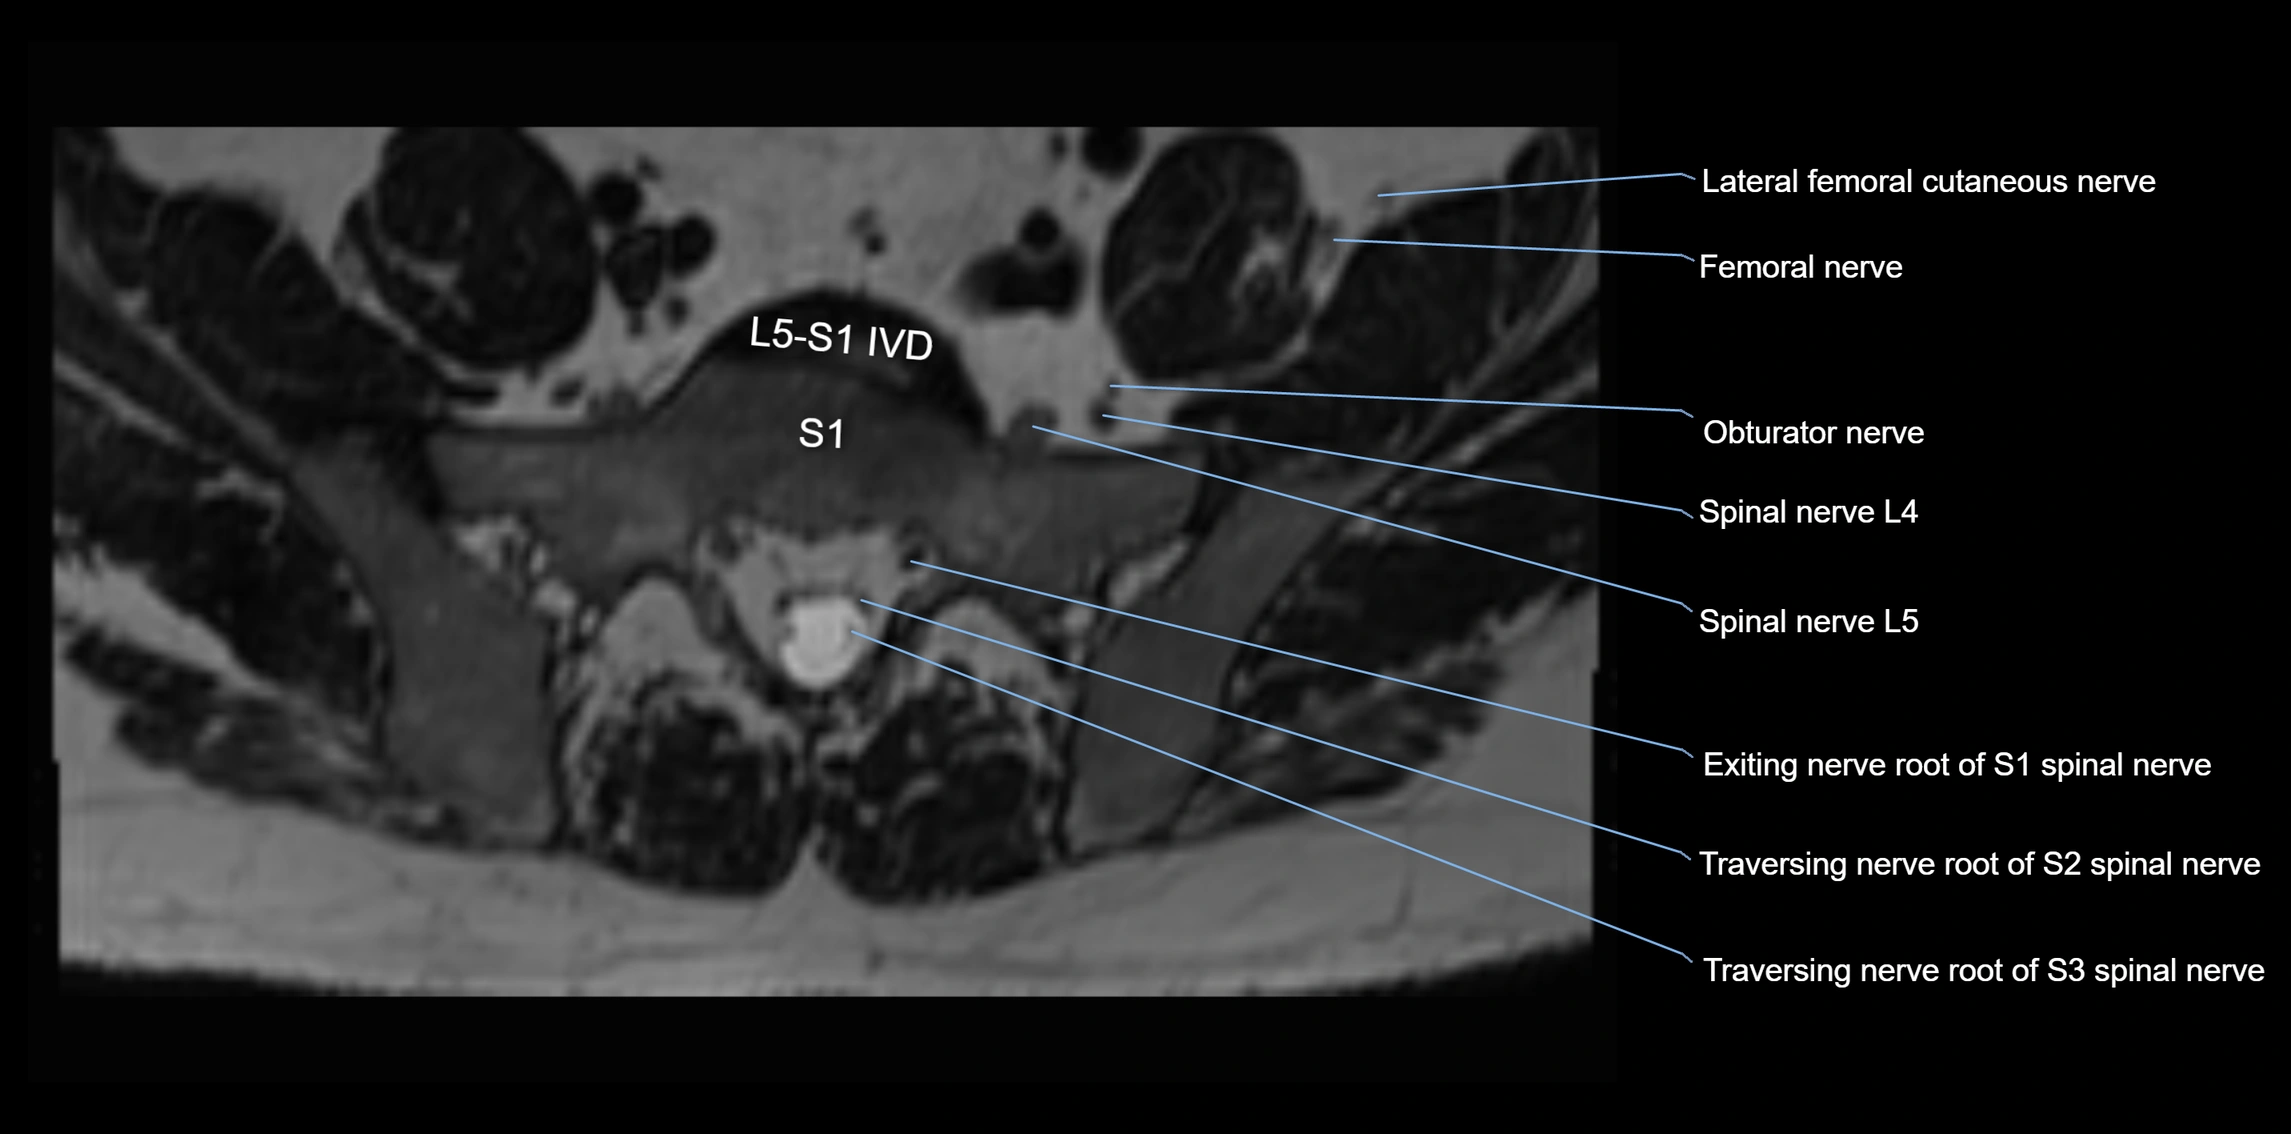

MRI image

image